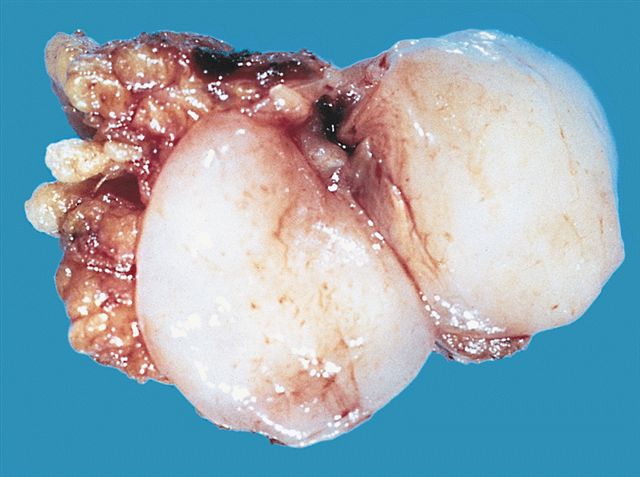

Gross description

- Typically these lesions are well circumscribed and multinodular

- Low grade tumors will have a gelatinous cut surface, with higher grade tumors showing a more solid fleshy appearance

Gross images